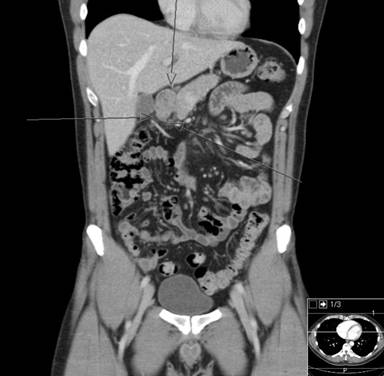

A 38-year-old male patient presented to the emergency room due to acute epigastric pain, nausea and vomiting. Physical examination revealed tenderness in the upper abdomen. Body temperature was 37.3°C. C-reactive protein was 113 mg/L (reference range: 0-3 mg/L) and his white blood cell count was raised (15.5 x109/L; reference range: 3.5-8.8 x109/L). Renal and liver function tests and serum pancreatic amylase were normal. He was otherwise healthy and was not taking any medications. Upper gastrointestinal endoscopy showed a subepithelial lesion in the gastric antrum (Figure 1). Abdominal computed tomography scan revealed a heterogeneous 4 cm malignant-looking lesion in the gastric antrum with suspected invasion of the perigastric fat (Figure 2). Endoscopic ultrasound (EUS) confirmed the presence of a subepithelial lesion in the antrum, that had heterogeneous appearance and involved all subepithelial layers of the gastric wall (Figure 3). An EUS-led fine needle aspiration (FNA) showed inflammatory cells only. The patient recovered symptomatically and blood tests normalized within 5 days. However, on the grounds of the imaging findings, malignancy could not be excluded and distal gastrectomy was performed. Histopathology of the surgical specimen confirmed the presence of ectopic pancreas in the gastric antrum (Figure 4a) but showed no cancer. However, there was both chronic and acute inflammation with neutrophil infiltration (Figure 4b). Twelve months following surgery he was asymptomatic.

Figure 2. A computed tomography scan showed a heterogeneous 4 cm malignant-looking lesion in the gastric antrum with suspected invasion of the perigastric fat tissue. |